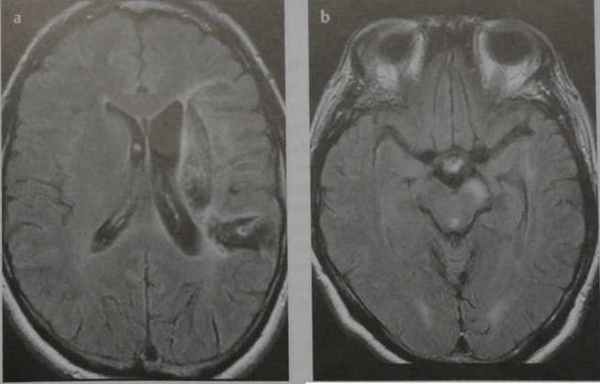

Валлеровская дегенерация вследствие инсульта в бассейне средней мозговой артерии в левом полушарии большого мозга. Р1_А1К-изображения (а, b) и Т2-ВИ в аксиальной плоскости (с). В зоне, кровоснабжаемой левой средней мозговой артерией, визуализируется кистозный дефект с глиозом (а). Определяется повышенная интенсивность сигнала от пирамидного пути в левой ножке мозга (b) и в продолговатом мозге слева (с).

Что покажут снимки МРТ головного мозга при валлеровой дегенерации

- Стадия 1 (острая): До 4 нед. после повреждения на традиционных МР-изображениях не определяются патологические изменения сигнала.

- Стадия 2 (подострая): Спустя 4-14 нед. на Т2-ВИ визуализируется гипоинтенсивная зона, обусловленная начальным, а не биохимическим распадом миелина и компонентов аксона.

- Стадия 3 (хроническая): Гиперинтенсивная зона на Т2-ВИ (распад жиров и липопротеинов, вазогенный отек, глиоз).

- Стадия 4: Атрофия